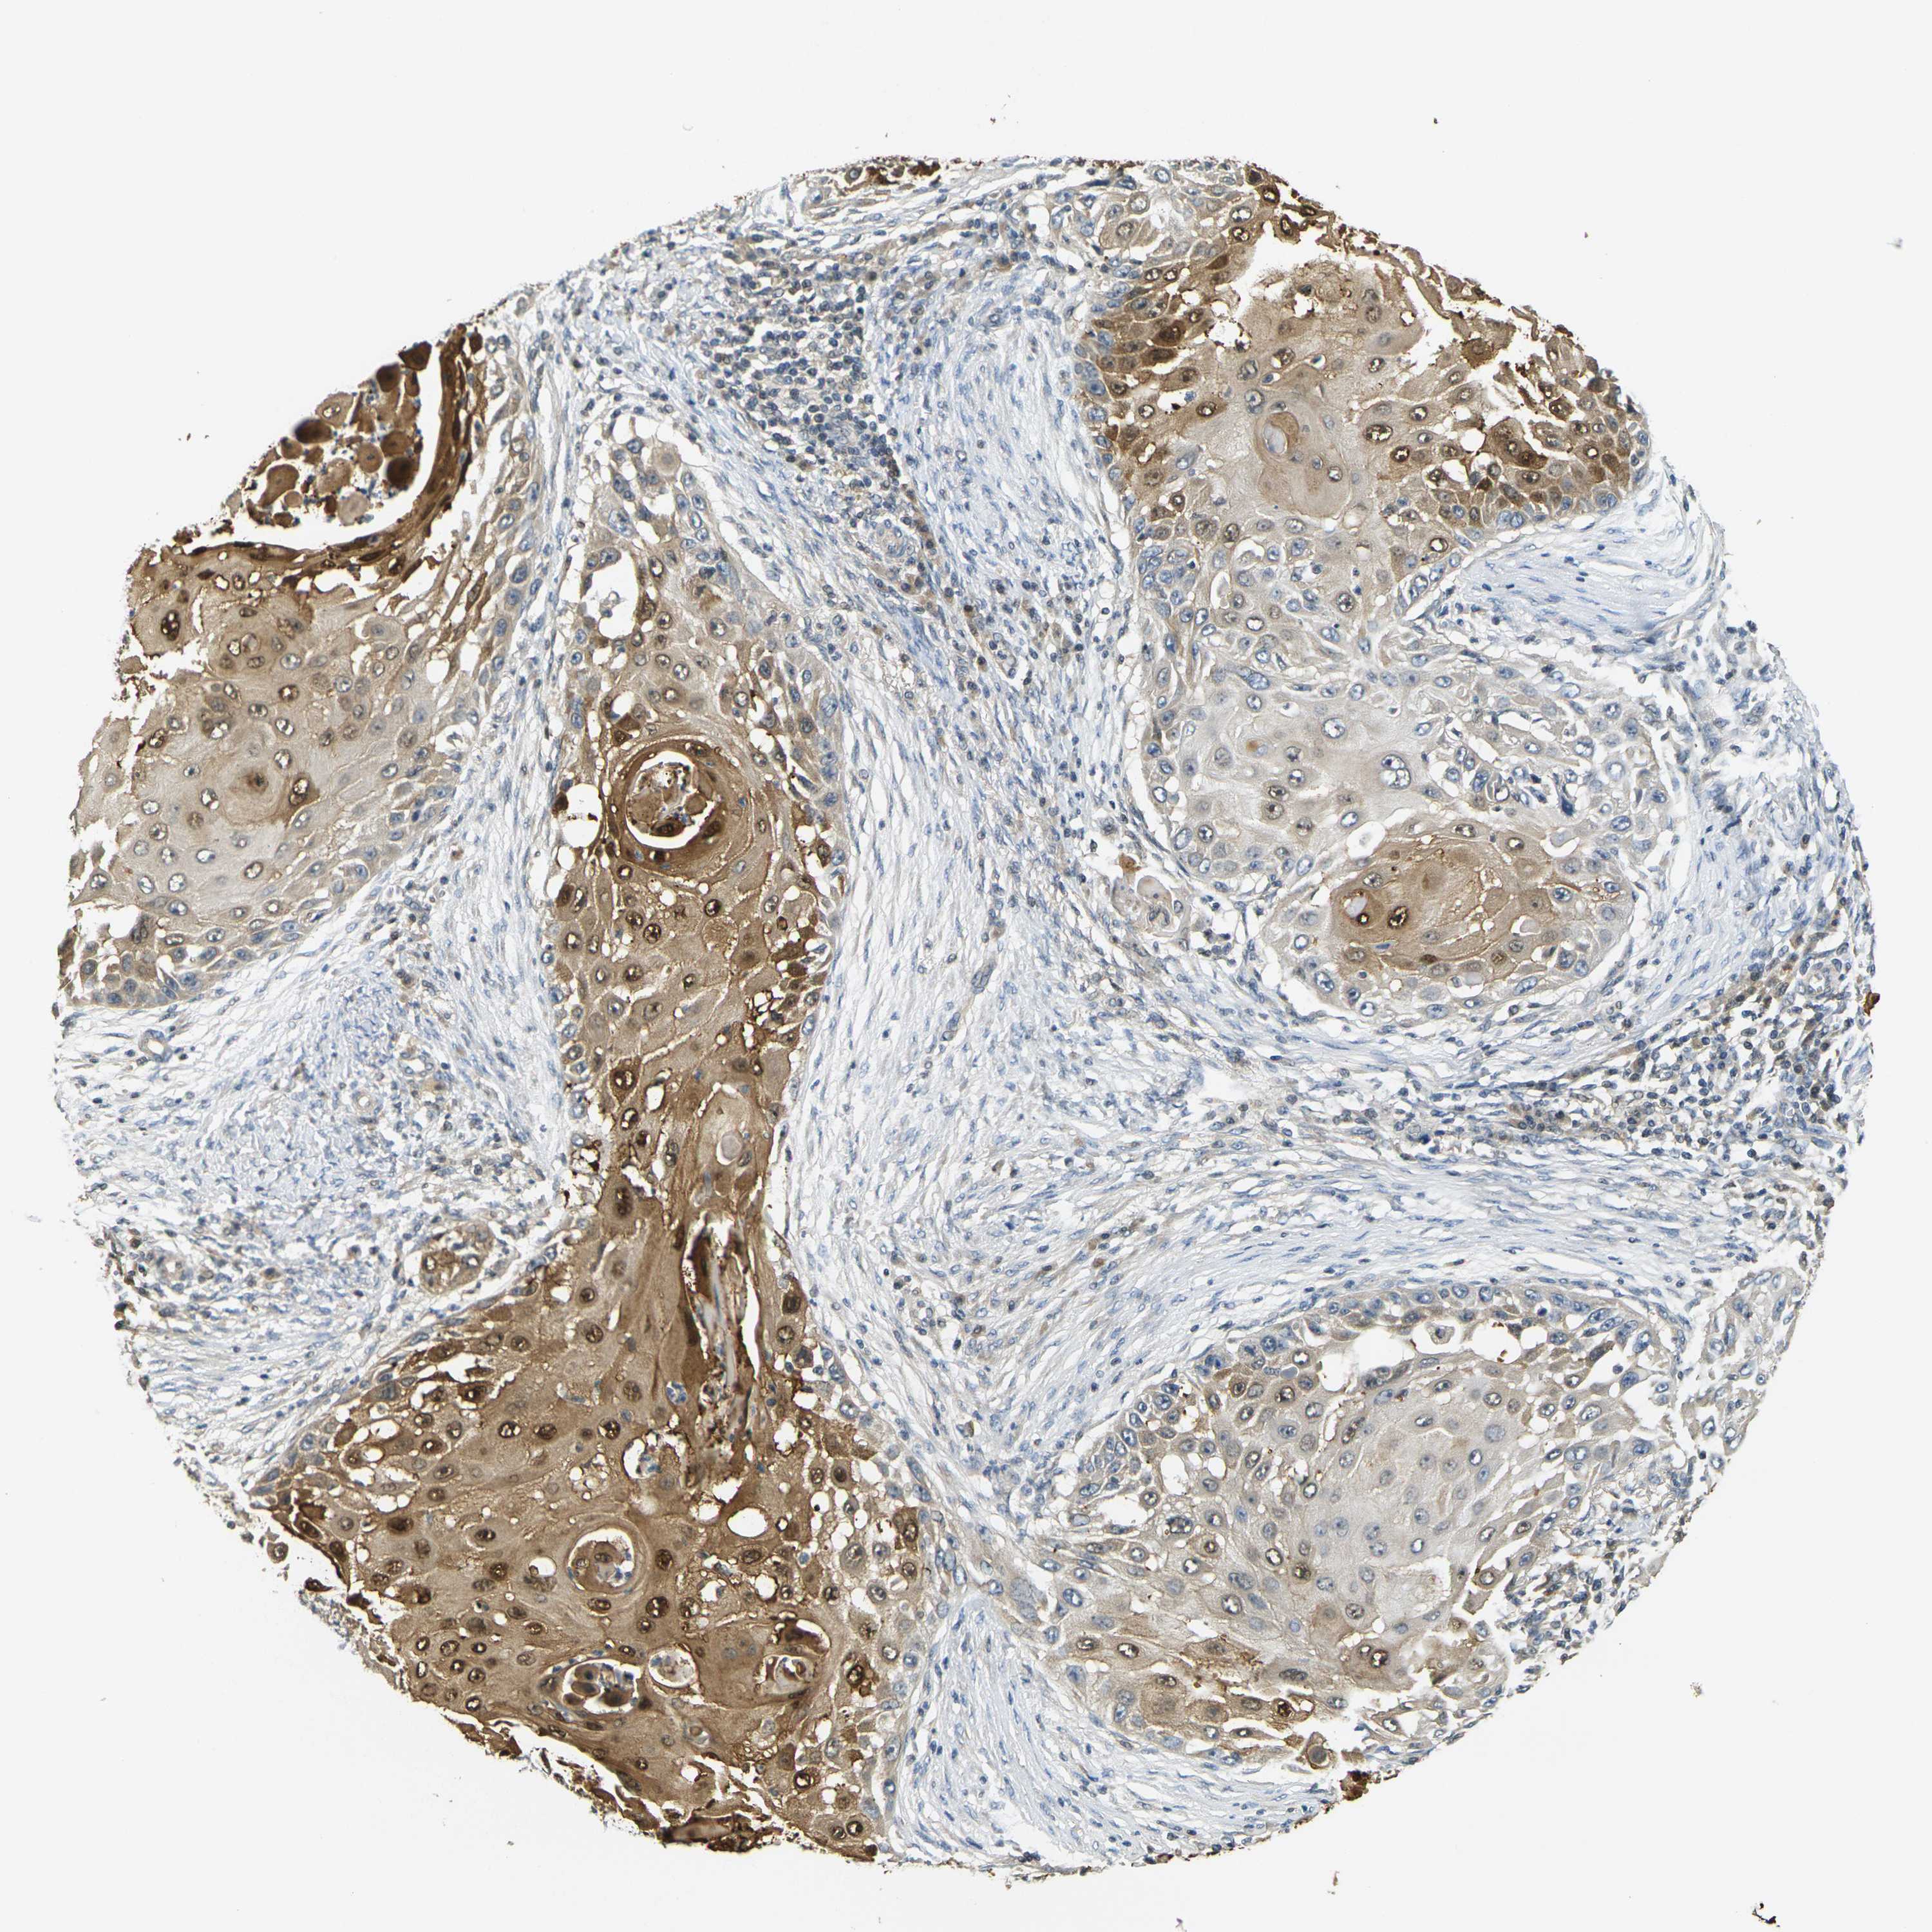

SKIN CANCER - Protein expressioni

A mouse-over function shows sample information and annotation data. Click on an image to view it in a full screen mode. Samples can be filtered based on level of antibody staining by selecting one or several of the following categories: high, medium, low and not detected. The assay and annotation is described here.

Each image is clickable and will lead to virtual microscopy that enables deeper exploration of all samples and also displays staining intensity scores, fraction scores and subcellular localization as well as patient and tissue information for each sample.

Antibody HPA013856

Antibody HPA017762

Squamous cell carcinoma, NOS

Basal cell carcinoma

Squamous cell carcinoma in situ, NOS

Squamous cell carcinoma, metastatic, NOS